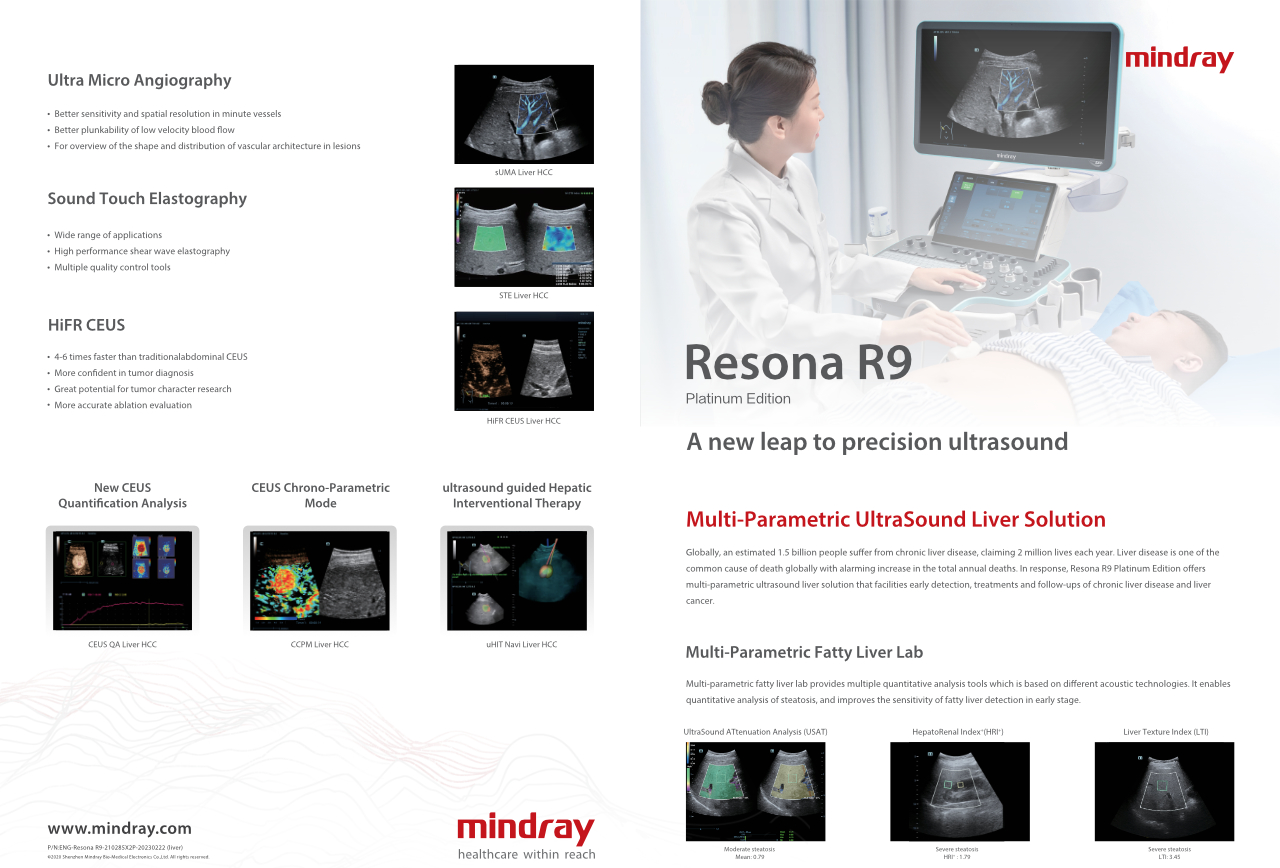

Resona R9 Platinum Edition

L'evoluzione dell'ecografia di precisione

Attraverso l'integrazione di una varietĂ di innovativi strumenti multiparametrici con un livello di nitidezza dell'immagine senza precedenti, Resona R9 Platinum Edition rappresenta l'evoluzione sia per l'uso clinico quotidiano che per la ricerca.

A livello globale, si stima che 1,5 miliardi di persone soffrano di malattie epatiche croniche, che causano 2 milioni di vittime ogni anno. Le patologie del fegato sono una delle piĂč comuni cause di morte a livello globale, con un allarmante aumento del numero totale di decessi annuali. In risposta, Resona R9 Platinum Edition offre una soluzione ecografica epatica multiparametrica che facilita la diagnosi precoce, i trattamenti e i follow-up delle malattie epatiche croniche e del cancro al fegato.